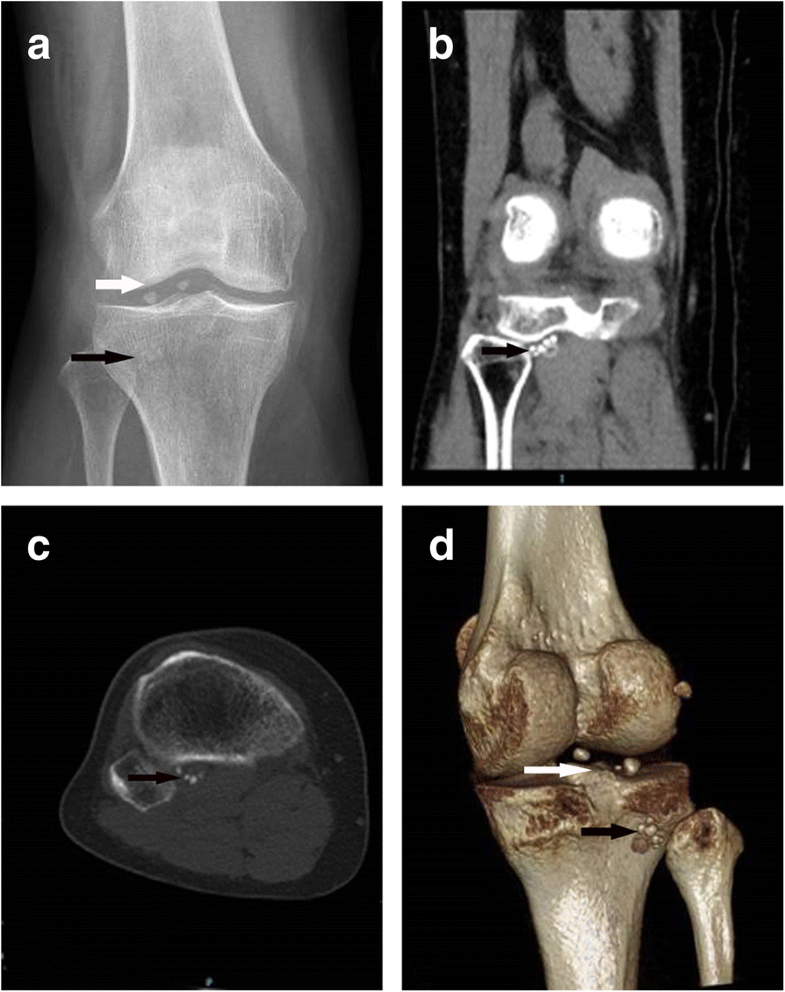

Figure 1 from Loose body as an obstacle for posterolateral arthroscopic portal formation in the Arthroscopic Knee Surgery Remove Loose Body Knee arthroscopic loose body removal. A minimally invasive procedure, surgeons perform loose body removal to remove fragments of bone, cartilage, or other loose tissue from the knee joint. Arthroscopy —this has become the surgery of choice for many. If you feel your knees locking up, consult an orthopedic surgeon to see if loose body removal is right for you. This. Arthroscopic Knee Surgery Remove Loose Body.

Arthroscopic removal of loose bodies using the accessory portals in the difficult locations of Arthroscopic Knee Surgery Remove Loose Body Most loose body removal procedures are done using one of the following techniques: Usually, arthroscopy surgery is needed to remove the loose bodies. Arthroscopy —this has become the surgery of choice for many. •begin with clear liquids and. Knee arthroscopic loose body removal. Knee arthroscopy is a minimally invasive surgical procedure. When it happens in the knee, the best way. Arthroscopic Knee Surgery Remove Loose Body.

Arthroscopic removal of loose bodies using the accessory portals in the difficult locations of Arthroscopic Knee Surgery Remove Loose Body Knee arthroscopic loose body removal. •begin with clear liquids and. Knee arthroscopy is a minimally invasive surgical procedure. When it happens in the knee, the best way to address this issue is to undergo a procedure called knee arthroscopic loose body removal. Arthroscopy —this has become the surgery of choice for many. Most loose body removal procedures are done using. Arthroscopic Knee Surgery Remove Loose Body.

Arthroscopic removal of loose bodies using the accessory portals in the difficult locations of Arthroscopic Knee Surgery Remove Loose Body This surgery only requires two small incisions. When it happens in the knee, the best way to address this issue is to undergo a procedure called knee arthroscopic loose body removal. Most loose body removal procedures are done using one of the following techniques: A minimally invasive procedure, surgeons perform loose body removal to remove fragments of bone, cartilage, or. Arthroscopic Knee Surgery Remove Loose Body.